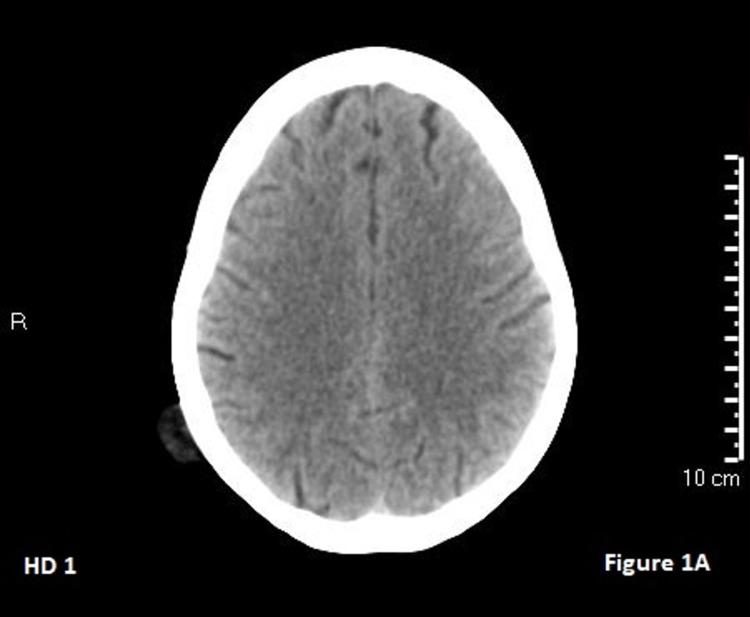

Posterior reversible encephalopathy syndrome (PRES) is a complex process that has been implicated in the setting of many chronic diseases (i.e., hypertension, chronic kidney disease, autoimmune diseases, infections, transplant treatments, etc.). The exact pathogenesis of PRES is still unclear; however, it has been suggested to involve endothelial injury leading to immune system activation and cytokine release. This case report examines an atypical presentation of PRES caused by serotonin-norepinephrine reuptake inhibitors (SNRIs).